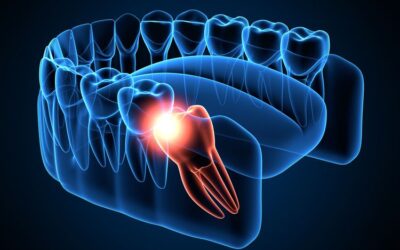

Gigi Geraham Bungsu Tumbuh? Apa Bahayanya?

Sahabat Ester, gigi geraham bungsu yang sedang tumbuh seringkali menimbulkan masalah, salah satunya adalah munculnya rasa sakit dan nyeri yang luar biasa. Gigi bungsu adalah gigi geraham terakhir yang terletak paling belakang. Gigi geraham bungsu umumnya tumbuh di...